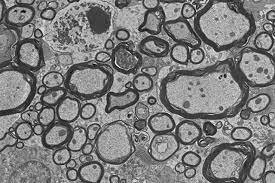

• Se inventa el Microscopio de electrones

Se inventa el Microscopio de electrones

Ernst Ruska inventa el microscopía electrónica, considerada uno de los mayores avances científicos del siglo XX, tiene importantes aplicaciones en muchos campos de la ciencia, entre ellos la biología y la medicina. Se ha utilizado para estudiar metales, virus, proteínas y moléculas.